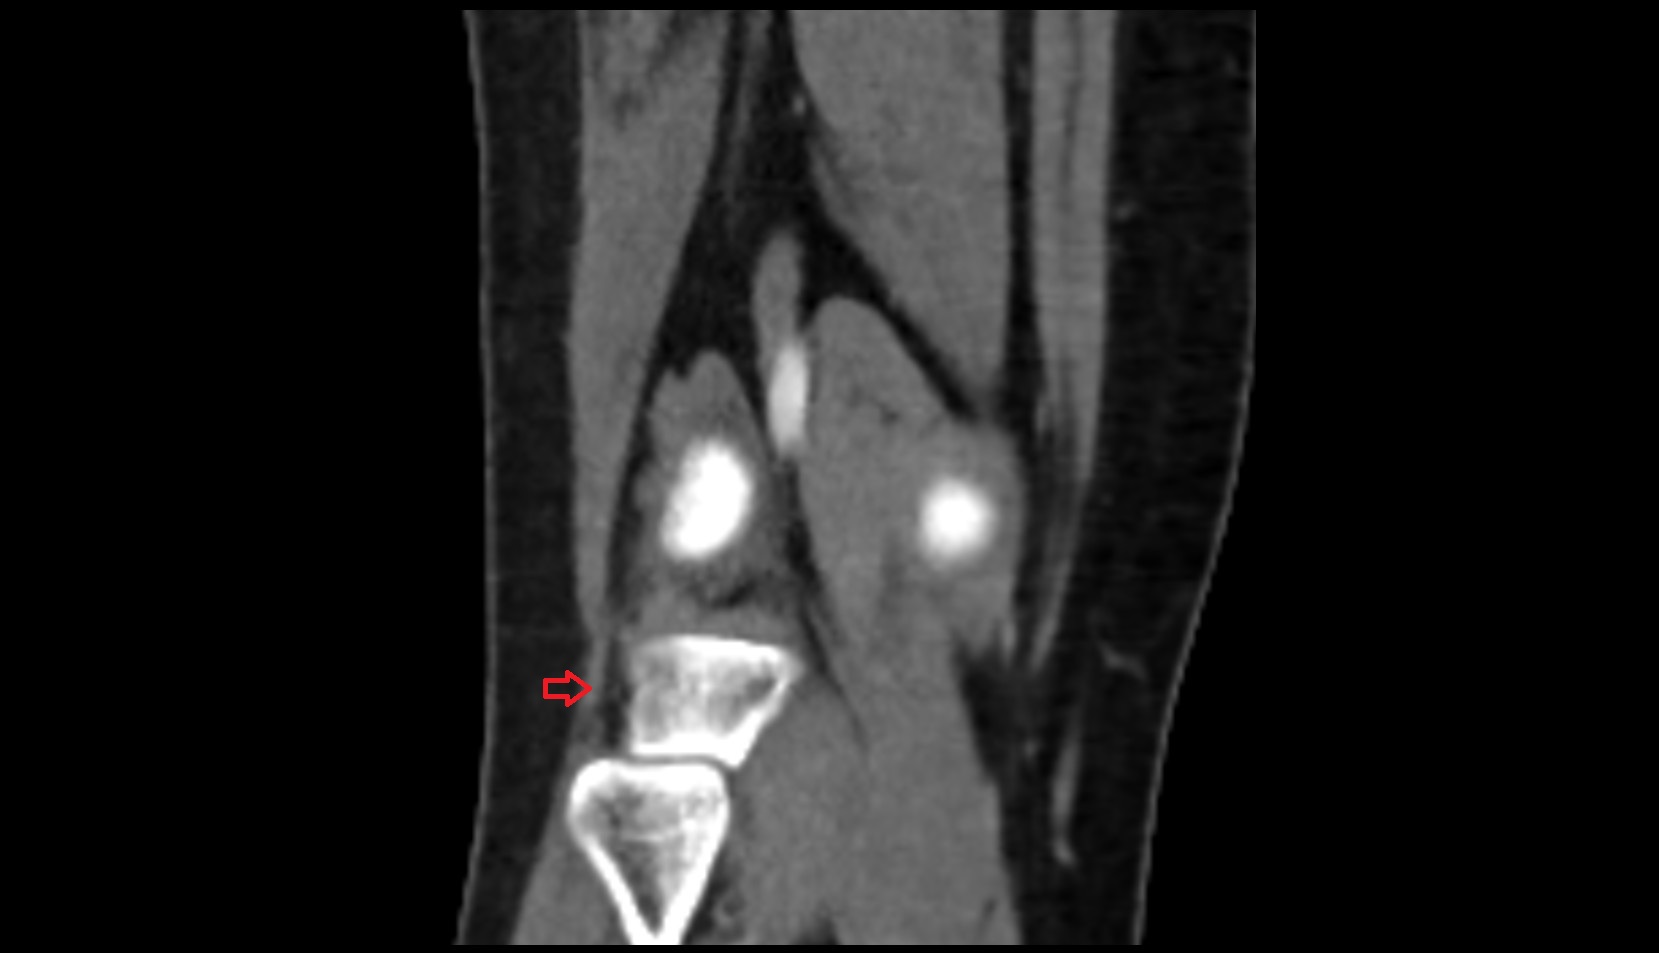

- Knee Joint